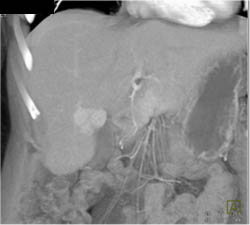

Hepatoma Invades the Inferior Vena Cava (IVC)